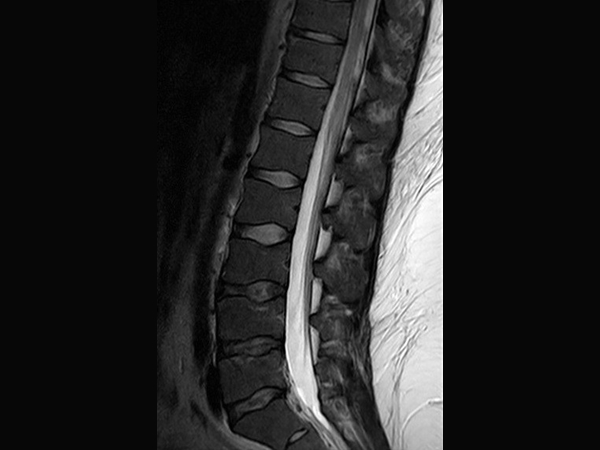

This is a lumbar spine examination of a young obese patient (170 kg) with right sciatic pain. The main difference in the protocol for this obese patient is that the voxel size is around 15-20% larger than in our standard protocol. This patient's weight will vastly increase the minimum TR requirements under the SAR modelling of any 3T scanner. The larger voxel helps both in reducing this increase in scan time and reduces SAR.The MultiTransmit technology evens out the flip angle and SAR across these large fields of view, even when filled with such a large patient, and the dStream coils and SmartSelect technology allows maximum penetration to allow for excellent SNR.The images demonstrate the high SNR provided by dStream and achieved with SmartSelect, which uses a quantitative method to determine and activate all coils that increase SNR. Imaging penetrated 150 mm of fat to reach this patient’s lower L-spine.

Sagittal T1w TSE